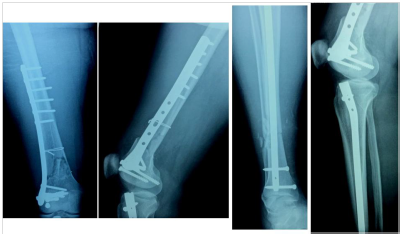

Figure 1 A-B, Preoperative x-rays (AP and lateral views) showing a Fraser type IIb floating knee.

Figure 2 A-B, same fracture treated by ORIF by condylar locking plate and IM nailing of tibia respectively.